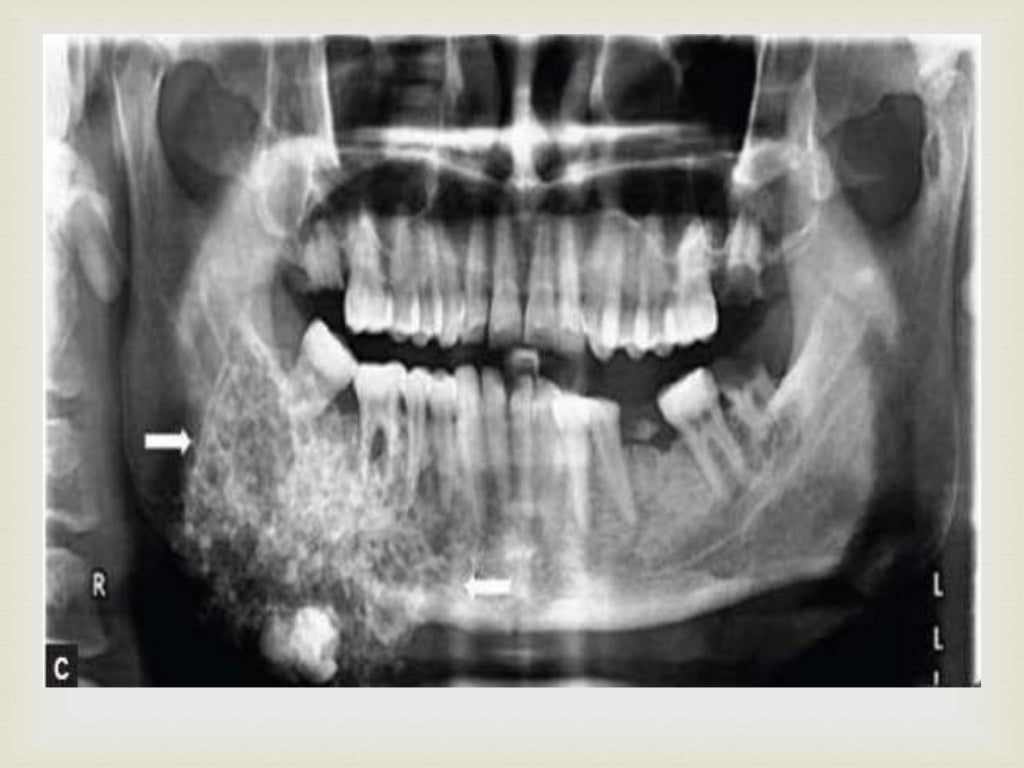

Radiographic appearance of cysts, tumors and fibro osseous lesions of Oral Cavity Tumor Definition What is the oral cavity? Oral cavity and oropharyngeal cancers start in the mouth or throat. oral cancer (mouth cancer) is the broad term for cancer that affects the inside of your mouth. Oropharyngeal cancer starts in the middle part of the throat just behind the oral. Oral cancer can look like a common problem with your lips or. Oral Cavity Tumor Definition.

Tumors of the oral cavity and oropharynx